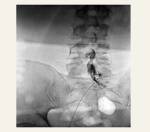

Epidurograma - Discograma

Prueba utilizada para diagnosticar si el dolor en la espalda es causado por un disco vertebral dañado. Es la única prueba que nos puede indicar con precisión si el dolor se origina en el disco intervertebral. La prueba se practica, bajo fluoroscopia, mediante la inyección de un contraste dentro del disco intervertebral que se encuentre dañado.